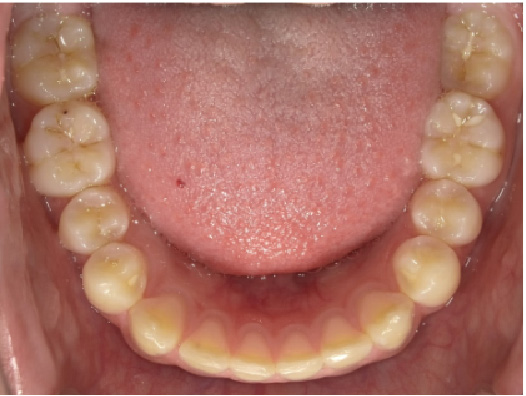

狭い歯列(狭窄歯列)によって、舌が歯列の中に収まらない状態です。

●高口蓋 ●低位舌 ●口呼吸

狭窄歯列(高口蓋)

狭窄歯列(低口蓋)

狭窄歯列(低位舌)

右のように、狭窄歯列だと舌は、狭い歯列に阻まれて、前方や上方の口蓋に自由に動くことができません。その結果、舌は低い位置(低位舌)にあり、前方に出ず後方に位置するので、気道が狭くなってしまっています。

一方、左のように、広い歯列だと舌は、前方にも上方にも自由に動けるので、舌は普段は口蓋についていて鼻呼吸が無理なくできているのです。

狭い歯列(狭窄歯列(きょうさくしれつ))

高口蓋(上顎が深い→鼻腔が狭い)

舌が歯列に納まらない→低位舌

歯並びが悪い

かみ合わせが悪い